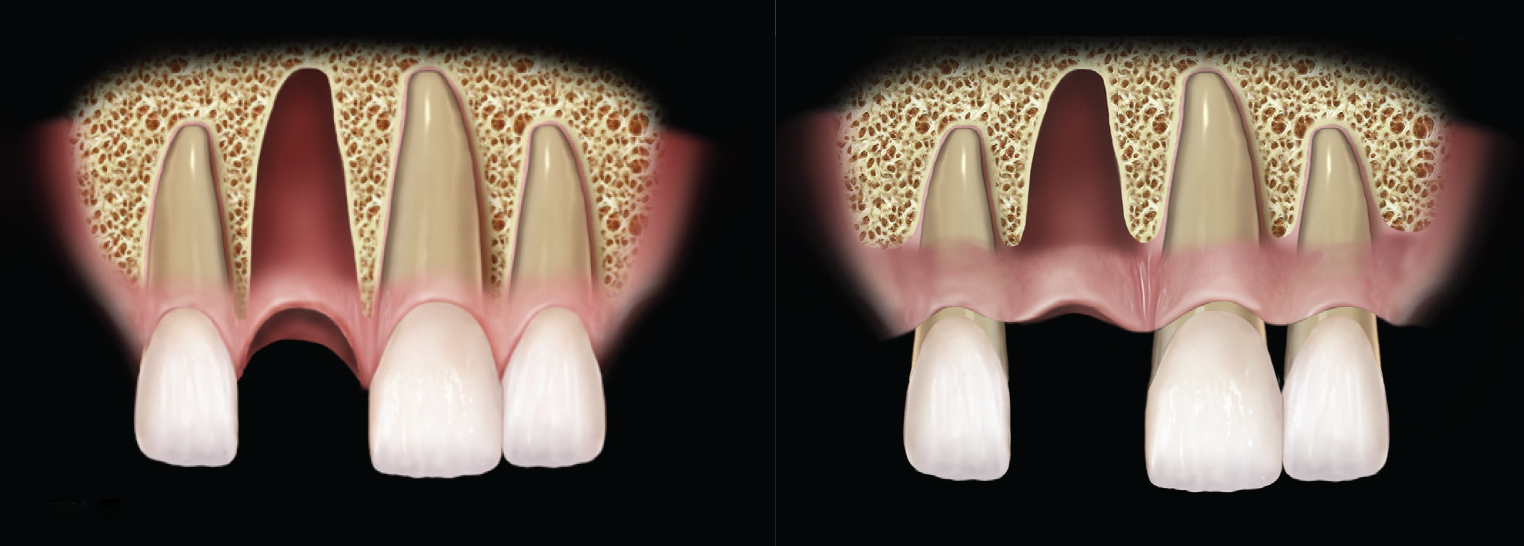

This classification of extraction sockets focuses on the bone topography of the extraction socket, while the protocol for treatment of each socket type is based on the biologic foundations of wound healing. The protocol takes into account the shape of the remaining bone, the biotype, and the location of the socket whether it be in the mandible or maxilla. First, an overview of fundamentals that led to this classification and treatment protocol will be presented, then a description of the socket classifications and treatment protocol for each socket type is discussed (Figure 1).

The basis of this classification is the hard tissue, as the presence and shape of the bone remaining after an extraction determines the foundational aspects of treatment. The bone topography of a socket determines the timing of implant placement and dictates the type of grafting techniques that may be needed, whether grafting in conjunction with implant placement, site preservation, or ridge augmentation. The bone topography of an extraction socket comprises the shape, contour, and 3-dimensional structure of the bone remaining following tooth extraction. It is determined by the shape of the alveolus apical to the extraction site, the level of interproximal bone, and the height, thickness, and quality of the buccal plate. Each of these aspects of the hard tissue affects the socket healing and treatment outcome, and these effects were considered when establishing this classification.

Interproximal bone levels influence the healing of the socket and the support of the interproximal soft tissue following implant placement. The presence or absence of papilla between an implant and a natural tooth is dependent on the level of interproximal bone. Therefore, the height of the interproximal bone plays a significant role in the final esthetic outcome when replacing a failing tooth with an implant-supported restoration.4,5

The interproximal bone affects the healing of an extraction socket, because this bone along with the buccal and lingual bone makes up the walls of a socket. After tooth extraction, a blood clot will form within the confines of the extraction socket walls; this blood clot will serve as the scaffold for bone formation, turning into woven and, then eventually, mature trabecular bone.6 As the interproximal, lingual, and buccal bone all support the initial blood clot, their height affects the dimension of the blood clot and, therefore, impacts the final bone morphology.

The quality of the bony walls present also affects the socket’s healing and, therefore, influences the morphology of the healed site. When the quality of the buccal plate is poor due to its being thin, made mostly of cortical bone, or dehisced, it is more likely to resorb and result in greater dimensional changes following socket healing.7 The dimensional changes that occur after tooth extraction related to the height and quality of the socket walls can be reduced through socket grafting or compensated for with the use of guided bone regeneration (GBR) simultaneous to tooth extraction.8,9 Grafting at the time of implant placement may also correct buccal plate loss; however, careful analysis of the quantity and quality of residual buccal plate must be made to achieve reproducible success.10,11

Principles of Periodontal Defect Repair

In this protocol, the principles observed in periodontal defect repair have been applied to extraction sockets. This is possible because of the similarities between sockets and periodontal defects: in both, the wound heals from the walls and continues to the center6; also, a completely intact socket is essentially a 4-wall defect within the alveolus, while a socket that is missing half of a buccal plate can be regarded as a three-and-a-half–wall defect, and one with no buccal plate can be considered a 3-wall defect. With periodontal defects, as the number and quality of bony walls decrease, so does the predictability of regeneration; therefore, each socket must be examined because the width of the defect, the number of walls, and the quality of the bone around it all impact the potential for regeneration.12-14 The authors have considered the variations in sockets that are possible following single-rooted tooth extraction and have divided these possibilities into 3 groups. The treatment protocol for each group considers the predictability of regeneration based on the principles of wound healing and tissue regeneration.

Grade I

Grade I sockets are the most ideal. Following tooth extraction, a socket that has an intact buccal plate, adequate interproximal bone, and satisfactory apical topography will fall into this category. In this classification, an intact buccal plate is defined as having no fissures or dehiscences and less than 25% loss of height (Figure 4, left; Figure 5, left). This percentage of buccal plate loss was selected as the cutoff based on the average root length of single-rooted teeth, which is 14.2 mm,25 and the amount of buccal plate that can be reliably regenerated during immediate implant placement. Adequate apical topography is defined as enough bone present apical to the extraction site to allow for engagement of 3 mm to 4 mm of a properly positioned immediate dental implant (Figure 2).1,2 Adequate interproximal bone is defined as no or mild (up to 2 mm) periodontal bone loss on the adjacent teeth as to allow for support of the interproximal soft tissue and to enable placement of the platform of an immediate implant in the proper apical-coronal position relative to the adjacent teeth while still being bordered by bony walls on the mesial and distal aspects26 (Figure 3, left).

Grade II sockets are differentiated from Grade I by the amount and quality of the remaining buccal plate. A Grade II socket has a fissure, dehiscence, or deficiency of the buccal plate totaling a 25% to 50% loss. Like Grade I sockets, they have adequate interproximal bone and apical topography (Figure 3, left; Figure 4, center; Figure 5, center).

Grade III

Grade III sockets are the most deficient and include any socket with inadequate apical topography, insufficient interproximal bone, or more than 50% loss of buccal plate. Inadequate apical topography is defined as not enough bone present apical to the extraction site to allow for implant placement and may be the result of bone loss caused by periapical lesions or concavities due to existing anatomy of the alveolus (Figure 4, right; Figure 5, right). Insufficient interproximal bone is defined as moderate-to-severe periodontal bone loss—greater than 2 mm on one or both of the adjacent teeth.